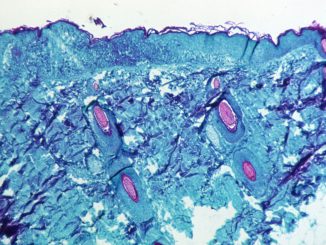

First suspected monkeypox case in state

by Ana B. Ibarra & Kristen Hwang for CalMatters CalMatters is an independent public journalism venture covering California state politics and government. For more info, visit calmatters.org. California reported its first case of suspected monkeypox yesterday […]